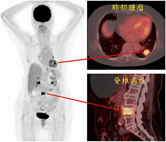

此病患最近半年飽受體重減輕及下背痛困擾,前來求診並進行健康檢查。

去氧葡萄糖正子掃描發現除了在後背疼痛處發現高葡萄糖代謝骨骼病灶之外,另外也在左肺發現有呈現葡萄糖攝取增加的肺部腫瘤及肺門淋巴結。根據造影的結果,顯示可能是惡性腫瘤併發轉移的現象。病患後續於門診接受近一步追蹤治療。